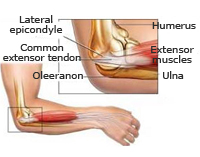

Fracturas de paleta humeral

La paleta humeral es la porción inferior del húmero que conecta con la parte superior del cúbito y radio formando la articulación del codo. Los traumatismos en esta región suelen producirse tras caída e impacto sobre la mano con el codo en extensión. Es necesaria una exploración neurovascular urgente para valorar lesiones en estructuras vasculares y nerviosas que pasan a este nivel y que se encargan del trofismo de la mano. El tratamiento se realizará en función del tipo de fractura y la edad del paciente con la finalidad de restituir, lo antes posible y sin secuelas, la funcionalidad de la articulación del codo.